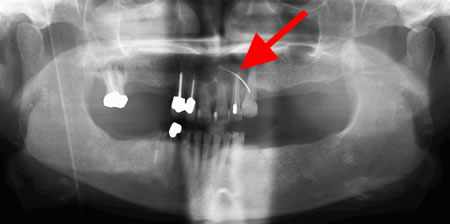

Panoramic radiograph showing decayed bilateral mandibular third molars and failed root canal treatment with periapical lesion related to the right mandibular first molar (middle arrow); also shows carious bilateral mandibular third molars on both sides

From the personal collection of Melanie S. Lang and Thomas B. Dodson